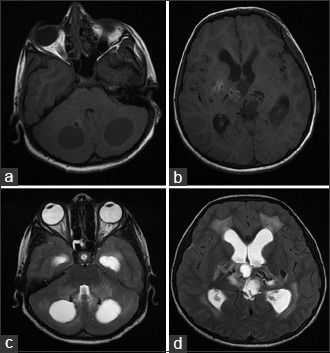

При визуализационных методах - нейросонографии (НСГ), рентгеновской компьютерной томографии (КТ), магнитно-резонансной томографии (МРТ) головного мозга - патогномоничным признаком синдрома Айкарди является агенезия мозолистого тела. Выделяют полную агенезию мозолистого тела, при которой отсутствуют все комиссуральные структуры вместе с фрагментами прозрачной перегородки, и частичную агенезию, которая в свою очередь подразделяется на агенезию ростральных и каудальных отделов мозолистого тела [29]. Чаще встречается агенезия каудальных отделов мозолистого тела, которая может сочетаться с изолированной дилатацией задних отделов боковых желудочков - кольпоцефалией. КТ-признаки агенезии мозолистого тела включают визуализацию межполушарной кисты, смещение вверх расширенного III желудочка и специфическое изменение формы тел боковых желудочков с увеличением расстояния между ними в виде симптома «ухвата» [7, 31]. Определяется расширение задних рогов боковых желудочков, своеобразный U-образный характер передних (фронтальных) рогов, удлиненная форма отверстия Монро. Кроме того, часто выявляются признаки атрофии вещества головного мозга в виде углубления и расширения конвекситальных борозд, расширения межполушарной и латеральной щелей, множественные пороки развития головного мозга.

Компьютерная томография показала признаки лакунарного черепа (определялись группы круглых, овальных или пальцевидных вдавлений на внутренней поверхности свода черепа, разделенные ребристыми выростами нормальной костной ткани в самых толстых частях лобной, теменной и верхней затылочной костей - характерный признак внутриутробного повышения внутричерепного давления или нарушения костеобразования - прим.пер.), а также обширные области интракраниальных кальцинатов, которые распространялись билатерально на глубокия* ядра мозжечка, границу белого и серого вещества, таламусы, область базальных ядер и капсулы.

а: на топограмме, которая проводится для разметки сканирования, хорошо видны лакунарный череп и интракраниальные кальцинаты.

b: КТ без контрастного усиления показала двусторонние кальцинаты в зубчатом ядре мозжечка;

с: несимметричная двусторонняя обширная кальцификация в области базальных ядер и внутренней капсулы, таламусов и

d: границы серого и белого вещества